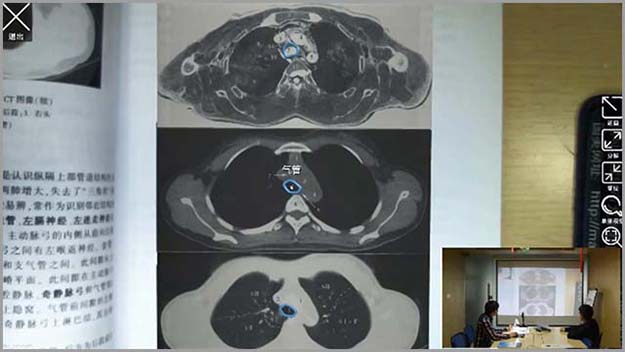

基礎醫(yī)學系列-增強現(xiàn)實醫(yī)學影(yΩ↑∏πǐng)像應用(yòng)解剖學

增強現(xiàn)實醫(yī)學影(yǐng)像應用(yòng)解剖學